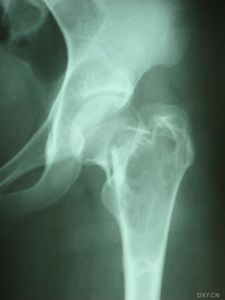

骨囊腫(UBC),又叫單純骨囊腫,其病變腔內充填為液體,四壁為薄的殼膜。單純性骨囊腫常發生於5到15歲的兒童,男性發病多於女性,比率約為2:1。病變部位多在長骨的乾骺端。最常見部位為肱骨近端,其次為股骨近端。活動性(active相對具有侵襲性的)骨囊腫靠近骨骺區,隨著兒童年齡增大,病灶會逐漸遠離骨骺,成為非活動性(inactive)。在年齡超過17歲的患者,病變會在非長管骨發生,如跟骨、骨盆等。

骨囊腫1.好發於4-20歲,多見於5-15歲兒童,少見於成人。好發於股骨頸、股骨上端和肱骨上端。隨著年齡增長,囊腫逐漸向骨幹方向移動。

骨囊腫臨床資料A組是待病理性骨折癒合後再治療骨囊腫,共48例,年齡為6-43歲之間;男39例,女9例。肱骨上端20例,肱骨中段6例,股骨上端9例其中(5例髖內翻),遠端3例,股骨頸2例,橈骨遠端2例,尺骨遠端1例,脛骨上端4例,腓骨頭1例。B組是囊腫及骨折一併治療,共6例,男5例,女1例。肱骨3例,股骨上端1例,股骨頸2例。